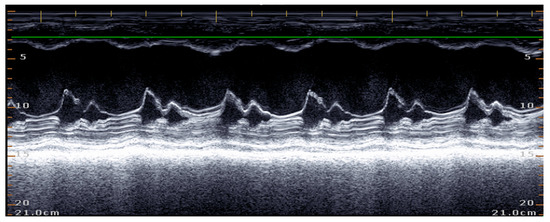

5.1.2. E-Point to Septal Separation or EPSS: An Echocardiographic Parameter for Accurate Assessment of Left Ventricular Performance